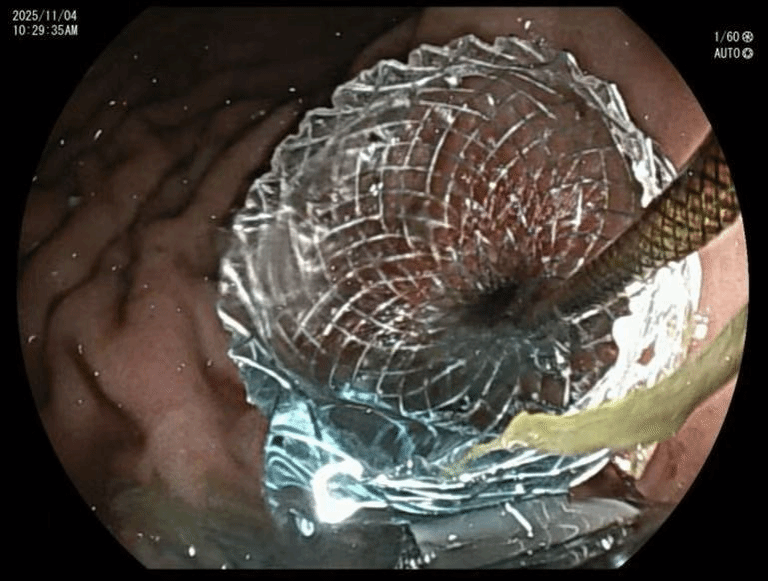

手术当天上午,消化科与麻醉科通力合作,消化科常虹主任医师、姚炜主任医师和张耀朋主治医师密切配合,在麻醉科鲍林主治医师的保驾护航下,将超声内镜送入郎先生胃内。在超声引导下,团队操作内镜精准定位到紧贴胃壁的空肠,通过特制的穿刺针,从胃内直接穿刺进入空肠,随后“释放”核心器械——一种特殊的“双蘑菇头”样金属支架。

术中成功放置支架

支架的两端如同伞面一样,在胃腔和空肠腔内打开,瞬间将胃壁和空肠壁紧紧拉拢在一起,一个全新的旁路就此建立。